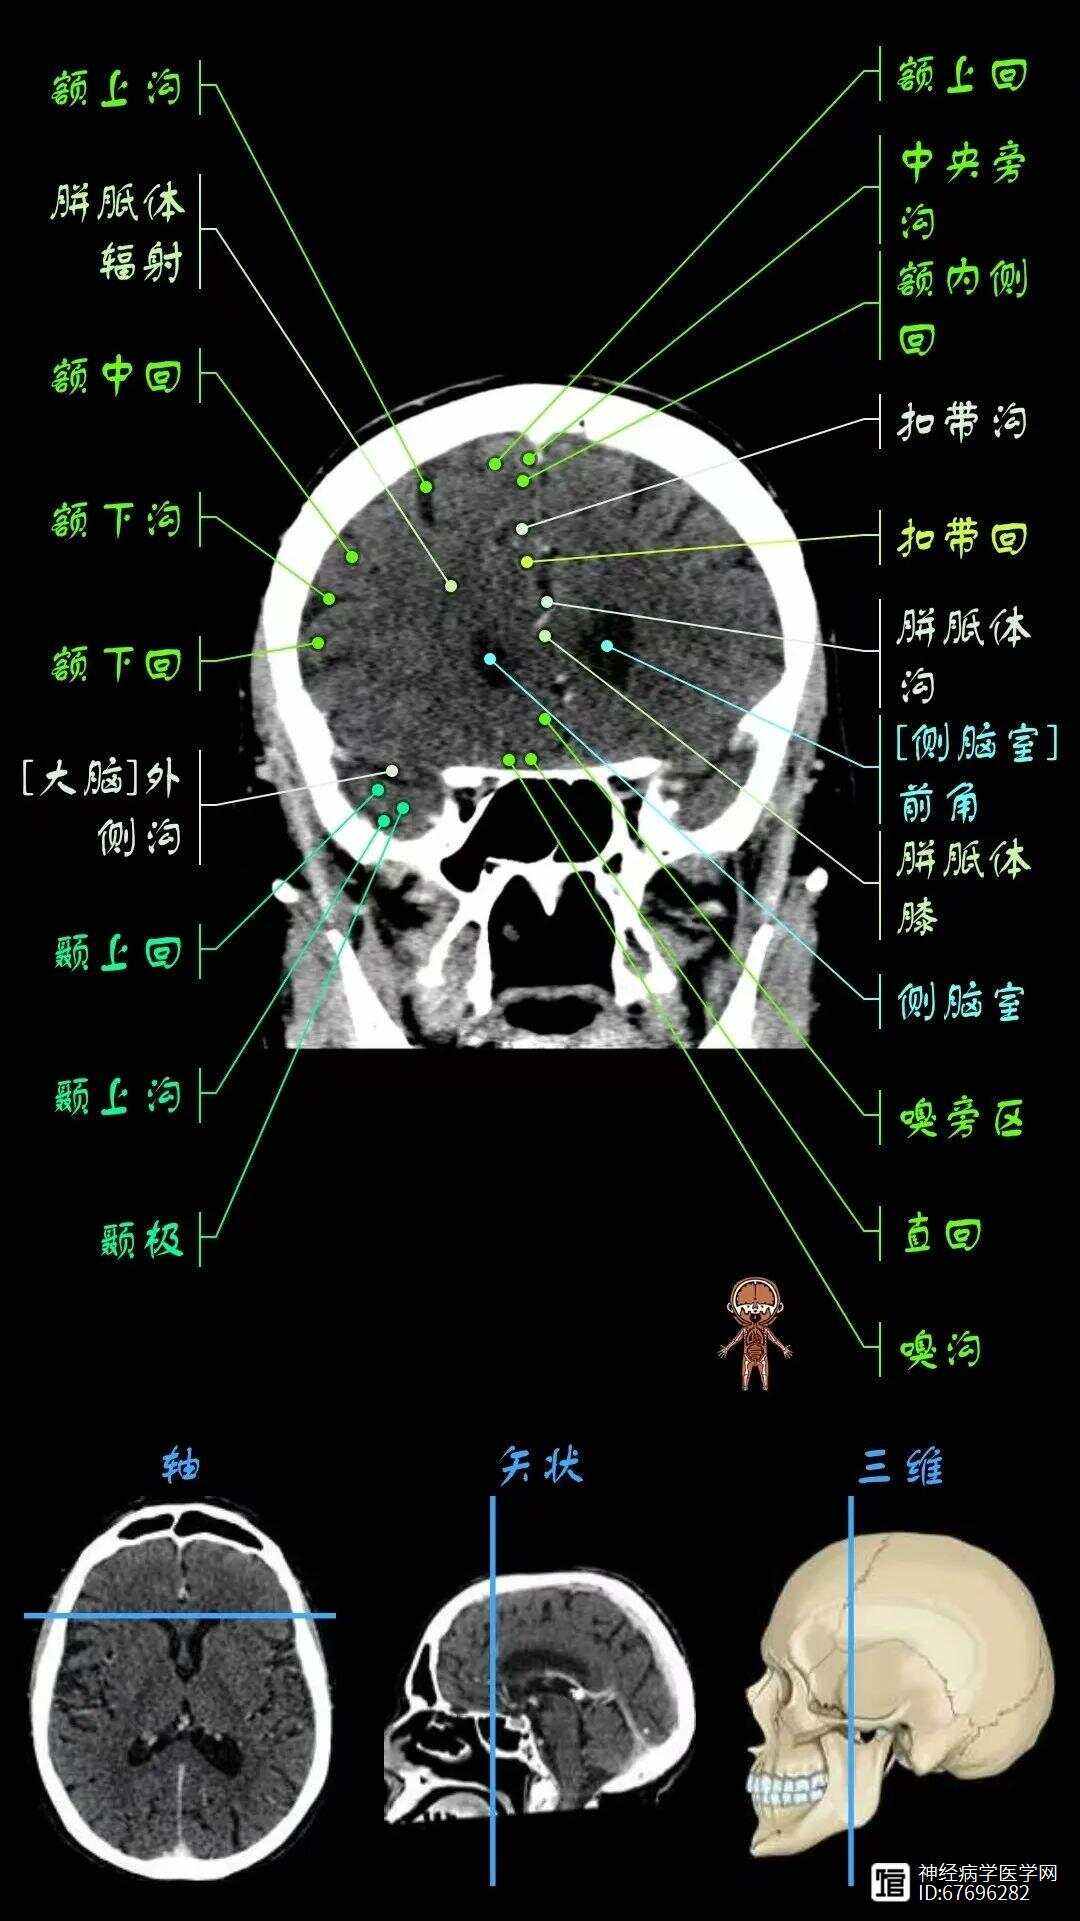

颅脑CT的价格根据检查方式和设备排数的不同而有所差异,具体如下普通CT平扫 普通CT平扫颅脑80元次 16排以下螺旋CT平扫颅脑170元次 16排螺旋CT平扫颅脑190元次 16排以上的螺旋CT平扫颅脑230元次 256排级以上的CT平扫颅脑300元次CT增强扫描 普通CT增强扫描颅脑90;颅脑CT能够发现颅内是否存在肿瘤性病变,为进一步的治疗提供影像学依据颅内感染性疾病如寄生虫病等,颅脑CT可以提供一定的诊断线索颅脑外伤虽然未直接提及,但颅脑CT也是评估颅脑外伤的重要手段鼻窦疾病如果合并鼻窦炎症鼻窦囊肿等疾病,颅脑CT也可以进行一定程度的检查需要注意的是 颅脑CT;颅脑断层解剖横断面将身体分为上下两部的纵切面矢状面将身体分为左右两部的纵切面冠状面将身体分为前后两部分的纵切面颅脑CT检查方法颅脑CT检查一般用横断面,扫描基线为眦耳线眼外眦与外耳道中心的连线或上眶耳线眦耳线向后倾20°角,层后8~10mm,连续8~10个层面颅脑MRI检查方法;头颅CT检查,适用于于颅内器质性病变,主要用于脑出血和脑梗死患者急性期的检查,如果是脑出血患者头颅CT检查表现为高密度病灶脑梗死患者头颅CT检查为低密度病灶,患者在发病24小时之内个别人可能会不显影,如果患者颅脑CT检查无脑出血,发病时间在6小时之内,躯体症状和体征严重时无溶栓禁忌证,适合溶栓的。